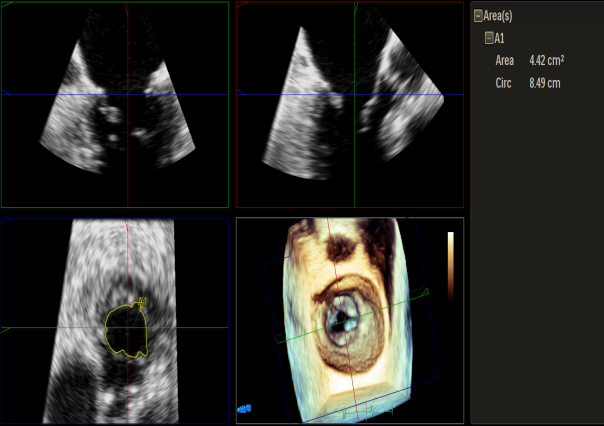

患者高龄、心衰时间较长、体型瘦小虚弱,无法耐受外科手术治疗,在门诊和入院初期评估时,由风湿性+功能性+退行性等多种原因导致的二尖瓣病变病理生理机制也给经导管介入治疗带来极大的挑战。门诊经胸超声心动图提示风湿性改变伴有轻度二尖瓣狭窄是传统意义上经导管缘对缘修复技术的禁忌,脱垂区后叶因AFMR参与被牵拉较短也是TEER的技术瓶颈。但患者反复心衰发作,病情恶化迅速,积极治疗重度的二尖瓣反流将是改善患者预后的一线生机。因此入院后我们通过经食道超声给这位患者进行了细致的评估后发现,患者的确有二尖瓣瓣叶增厚的改变,跨瓣压差在3-5mmHg,二尖瓣瓣口面积在4.43cm²,并没有明显的开放受限,瓣膜面积相对来说是TEER治疗的临界水平,后叶长度约7mm,尽管相对较短,在我们前期的TEER治疗患者中也可以达到充分的钳夹长度。因此经过心脏团队反复的综合评估,认为该患者有TEER治疗成功的机会,在充分药物治疗,患者心衰症状改善且病情平稳后,在患者以及家属强烈要求下,我们积极完善术前准备,择期行TEER治疗。

Qlab软件勾画估测瓣口面积约:4.42cm²

二尖瓣口平均跨瓣压差:5mmHg